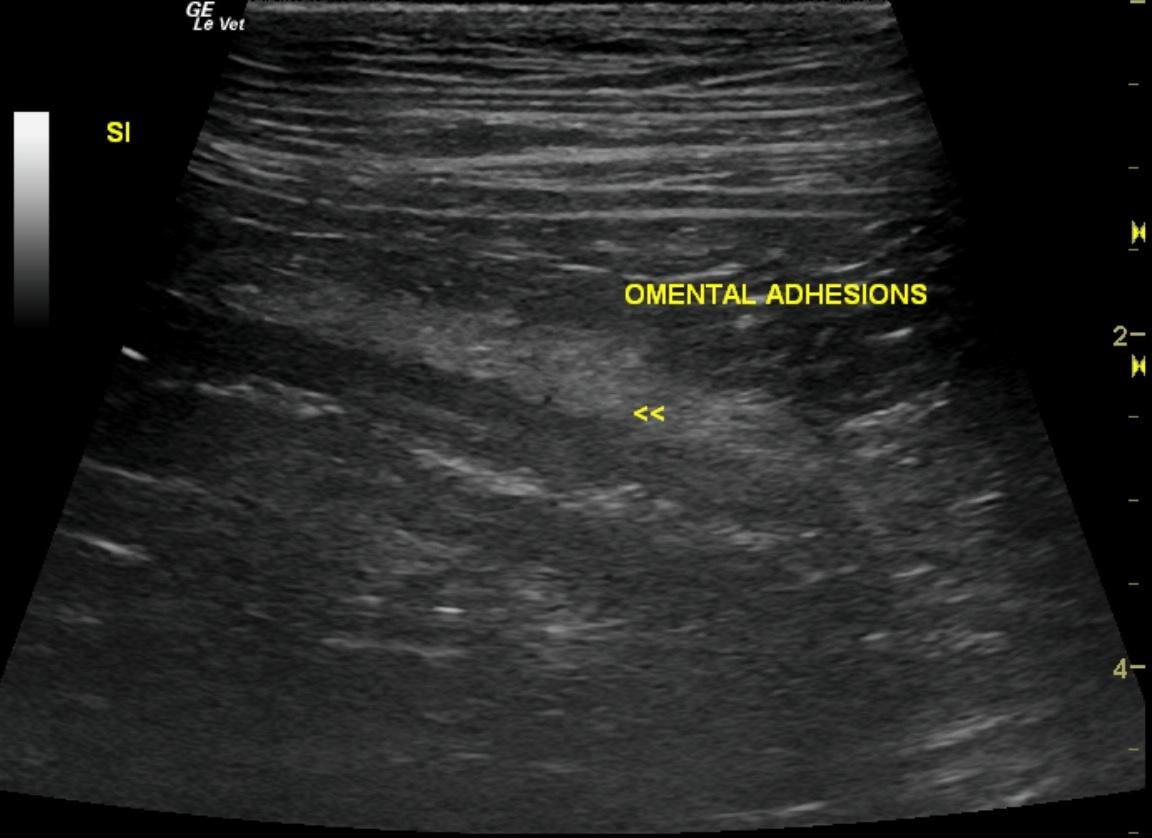

Colonic foreign body, intestinal adhesions in a 5 year old FS Bulldog

Video 1: stool material vs colonic foreign body;Video 2: Suspected mesenteric adhesions vs acute local inflammatory response caused by the passing of the foreign body

Video 1: 6 cm shadowing focal shadowing structure was noted in the descending colon at the level of the urinary bladder. Video 2: In the distal small intestine, multiple omental adhesions were noted associated with the jejunum in the right caudal abdomen.

Colonic foreign body, and intestinal adhesions